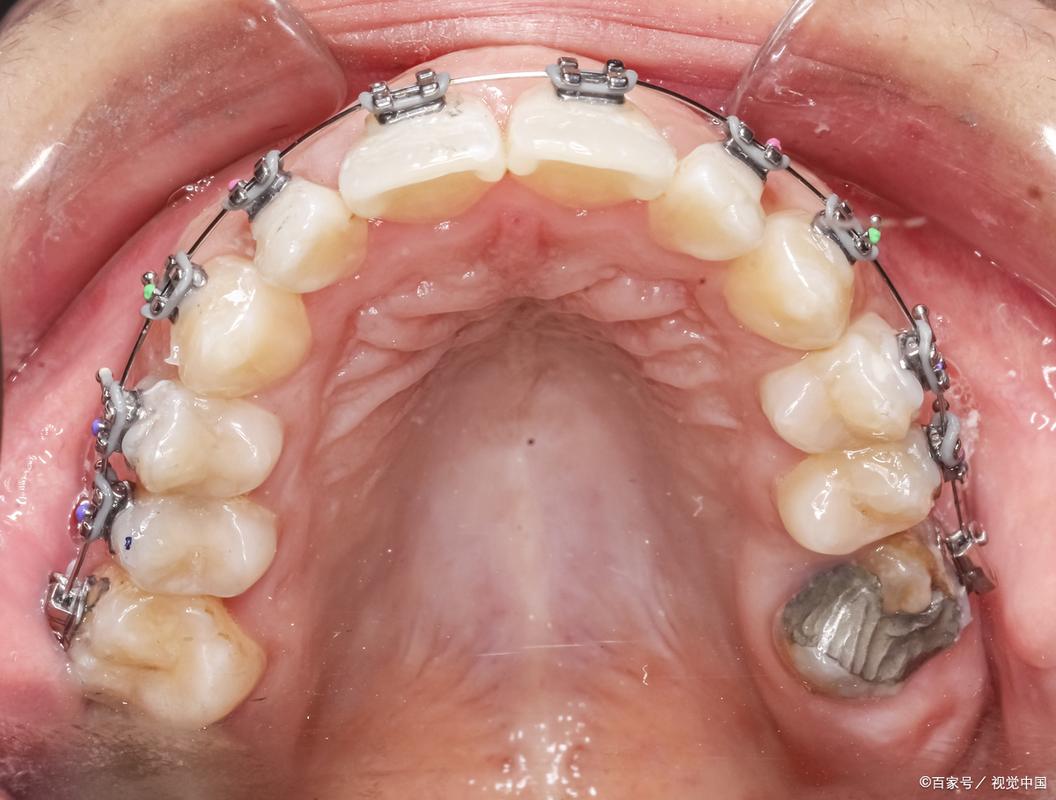

牙齿正畸治疗中,磨牙作为口腔中体积最大、咀嚼功能最强的牙齿,其位置、移动方向及稳定性对整个矫治效果至关重要,磨牙不仅承担着主要的咀嚼任务,还在维持咬合平衡、面部垂直高度及颌骨关系中发挥核心作用,正畸治疗中,无论是通过传统托槽矫治器还是隐形矫治器,磨牙的移动与调整往往是矫治计划的关键环节,涉及生物力学、解剖学及临床技术的综合应用。

在正畸治疗中,磨牙的功能意义远超其解剖结构,磨牙可作为支抗单位,为前牙移动提供稳定支撑(如内收前牙时,通过磨牙的稳定性避免支抗丧失);磨牙的位置直接影响咬合平面、面部垂直高度及颞下颌关节(TMJ)功能,上颌磨牙垂直向伸长可能导致前牙深覆颌加重,而下颌磨牙近中移动可能引发III类错颌畸形,正畸医生需通过精确的生物力学控制,实现磨牙在三维空间(近远中、垂直向、颊舌向)的合理调整。

磨牙颊舌向调整

适应症:磨牙颊倾或舌倾导致的中线偏斜、后牙反颌或锁颌,通过颊舌向移动调整磨牙位置,恢复咬合接触,常用技术包括:

- 固定矫治器:通过在磨牙上放置颊面管,配合弓丝的第三序列弯曲(转矩控制)调整牙根位置。

- 扩弓装置:如螺旋扩弓器,适用于上颌磨牙腭向移位导致的后牙反颌,通过扩大牙弓宽度实现磨牙颊向移动。